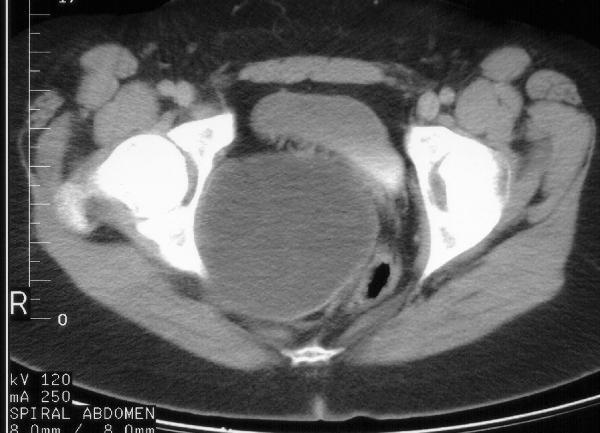

An 18-year-old girl has primary amenorrhea and recurrent UTIs. Her pelvic ultrasound shows a large cystic lesion. CT imaging is shown in exhibit 1. The most frequent associated condition is:

1

This patient has a hematocolpos due to vaginal obstruction, the Mayer-Rokatanski-Kuster-Hauser syndrome which occurs in 1:4000 female births. This syndrome is composed of vaginal agenesis or absence with a rudimentary uterus, normal ovaries, and normal external genitalia. Absence or agenesis of the vagina is a developmental error of the ureterovaginal canal or the vaginal plate with failure of mullerian duct fusion. Renal anomalies are common with over one third of patients noted to have renal agenesis, ectopia or fusion abnormalities. Skeletal anomalies have been reported in 12% of girls and usually involve the spine, limbs or ribs. Diagnosis of this condition is made most often at the time of puberty in association with amenorrhea. Occasionally, it is noted in the neonatal period when evaluating a pelvic mass.